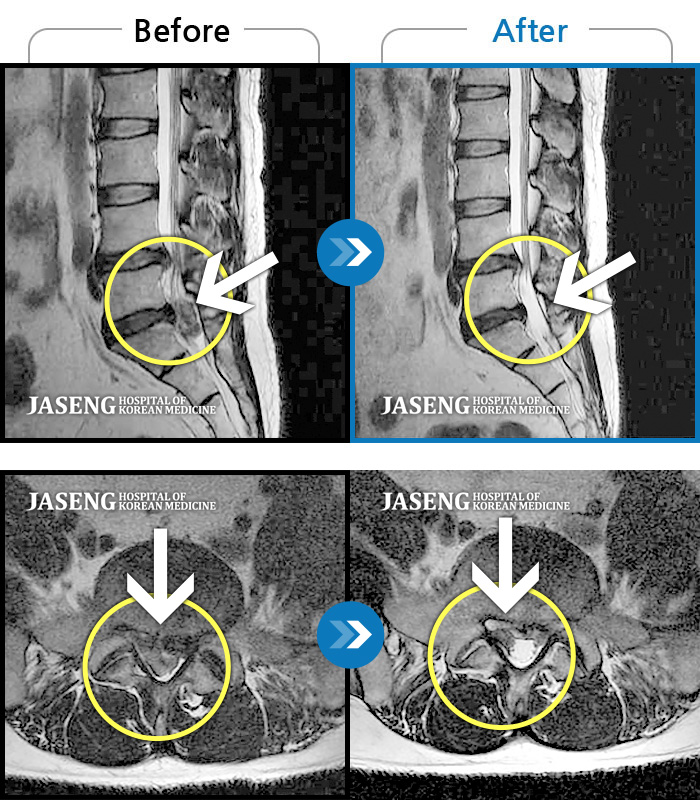

허리디스크

잠실 · 한상욱 원장

허리가 많이 아프고 왼쪽 다리가 저려 움직이기가 힘들다.

촬영시기

2022.01.19 ~ 2022.11.14

2022.12.02